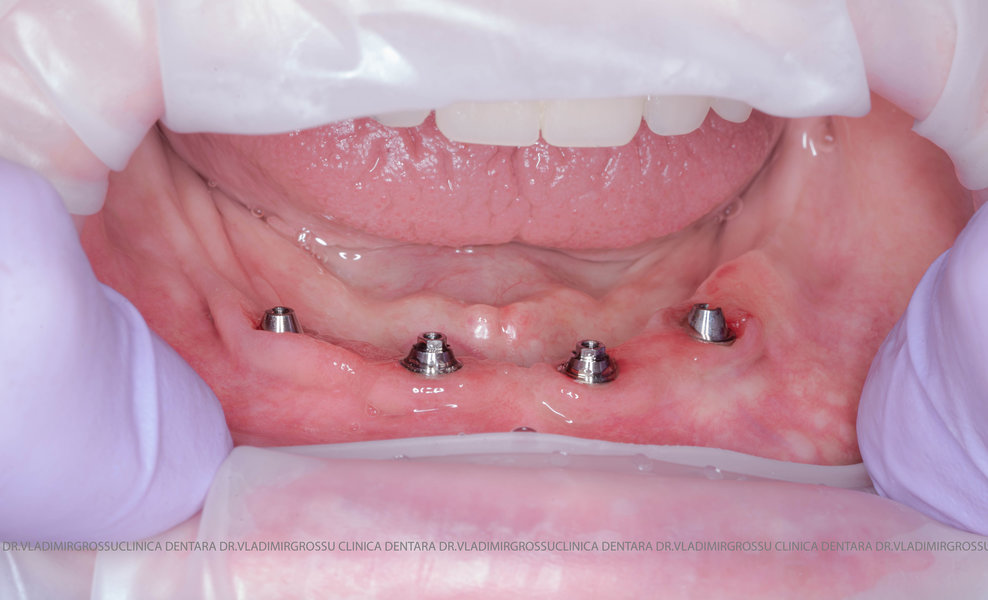

Această metodă este recomandată pacienților edentați total sau celor cu lipsuri dentare multiple. Procedura se realizează într-o singură etapă, iar pacientul primește proteza provizorie în ziua următoare intervenției. De regulă, proteza provizorie este realizată din masă plastică frezată. Suturile se îndepărtează după 5-7 zile.

La aproximativ 6 luni de la prima etapă, pacientul revine pentru protezarea definitivă. În această fază, medicul lucrează la nivelul multiunit-urilor și nu direct pe implanturi, ceea ce reduce riscurile pentru implant în etapa protetică.

- 4 implanturi;

- 2 multiunit-uri drepte și 2 multiunit-uri angulate, conform necesităților protetice;

- 4 abutment-uri provizorii pe multiunit-uri;